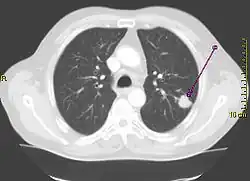

Para evaluar enfermedades relacionadas con la exposición al asbesto, se necesita un historial médico completo, un examen físico y pruebas de diagnóstico. La radiografía de tórax es la mejor herramienta para detectar en los pulmones cambios que resultan de la exposición al asbesto. Pruebas de la función pulmonar y sondeos computarizados en tres dimensiones del pulmón también ayudan en el diagnóstico de enfermedades relacionadas con el asbesto.

- Estudios radiológicos: estos estudios utilizan rayos X, campos magnéticos, ondas sonoras o sustancias radiactivas para crear imágenes del interior del cuerpo. Con frecuencia se efectúan varios estudios radiológicos para detectar el cáncer de pulmón y determinar la parte del cuerpo adonde haya podido propagarse. Se lleva a cabo una radiografía de tórax para ver si existe alguna masa o mancha en los pulmones.

- La tomografía axial computarizada (TAC): da información más precisa acerca del tamaño, la forma y la posición de un tumor, y puede ayudar a detectar ganglios linfáticos engrosados que podrían contener un cáncer procedente del pulmón. Las tomografías computarizadas son más sensibles que las radiografías de tórax de rutina para detectar los tumores cancerosos en etapa inicial.